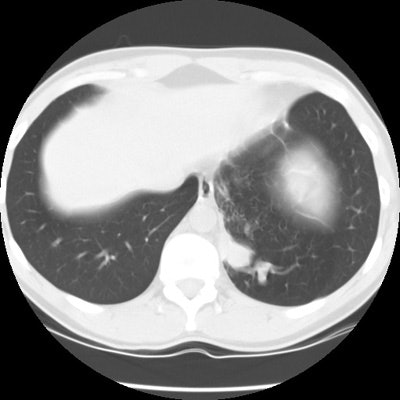

CT scan revealed a soft tissue mass in the left posterior-medial lung which had a branching tubular appearance. Some associated para-emphysematous changes were noted. (Click images to enlarge)